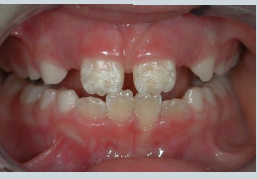

what is shown here?

enamel hypoplasia → not the same as hypo-mineralisation

Ameloblasts affected during development – less enamel formed Pits, grooves, thinning

enamel hypoplasia vs hypomineralisation

hypo-mineralisation is when you get the correct thickness of enamel but its softer and wears away faster

hypoplasia - structure is okay - but thinner, incomplete or pitted

what could be the causes of enamel hypoplasia? 6

Nutritional deficiencies

Vitamin D / Calcium deficiency

Pre/Perinatal issues

Maternal infections e.g. rubella and syphilis

Prematurity / Low birth weight

Infectious diseases

Febrile illnesses in early childhood

Measles, chickenpox, scarlet fever

Endocrine

Hypoparathyroidism (abnormal calcium/phosphate

regulation)

Hypothyroidism – delayed tooth eruption

Chronic Renal Disease – disrupting calcium/phosphate

Coeliac Disease – nutrient malabsorption

genetics

amelogenesis imperfecta

down syndrome